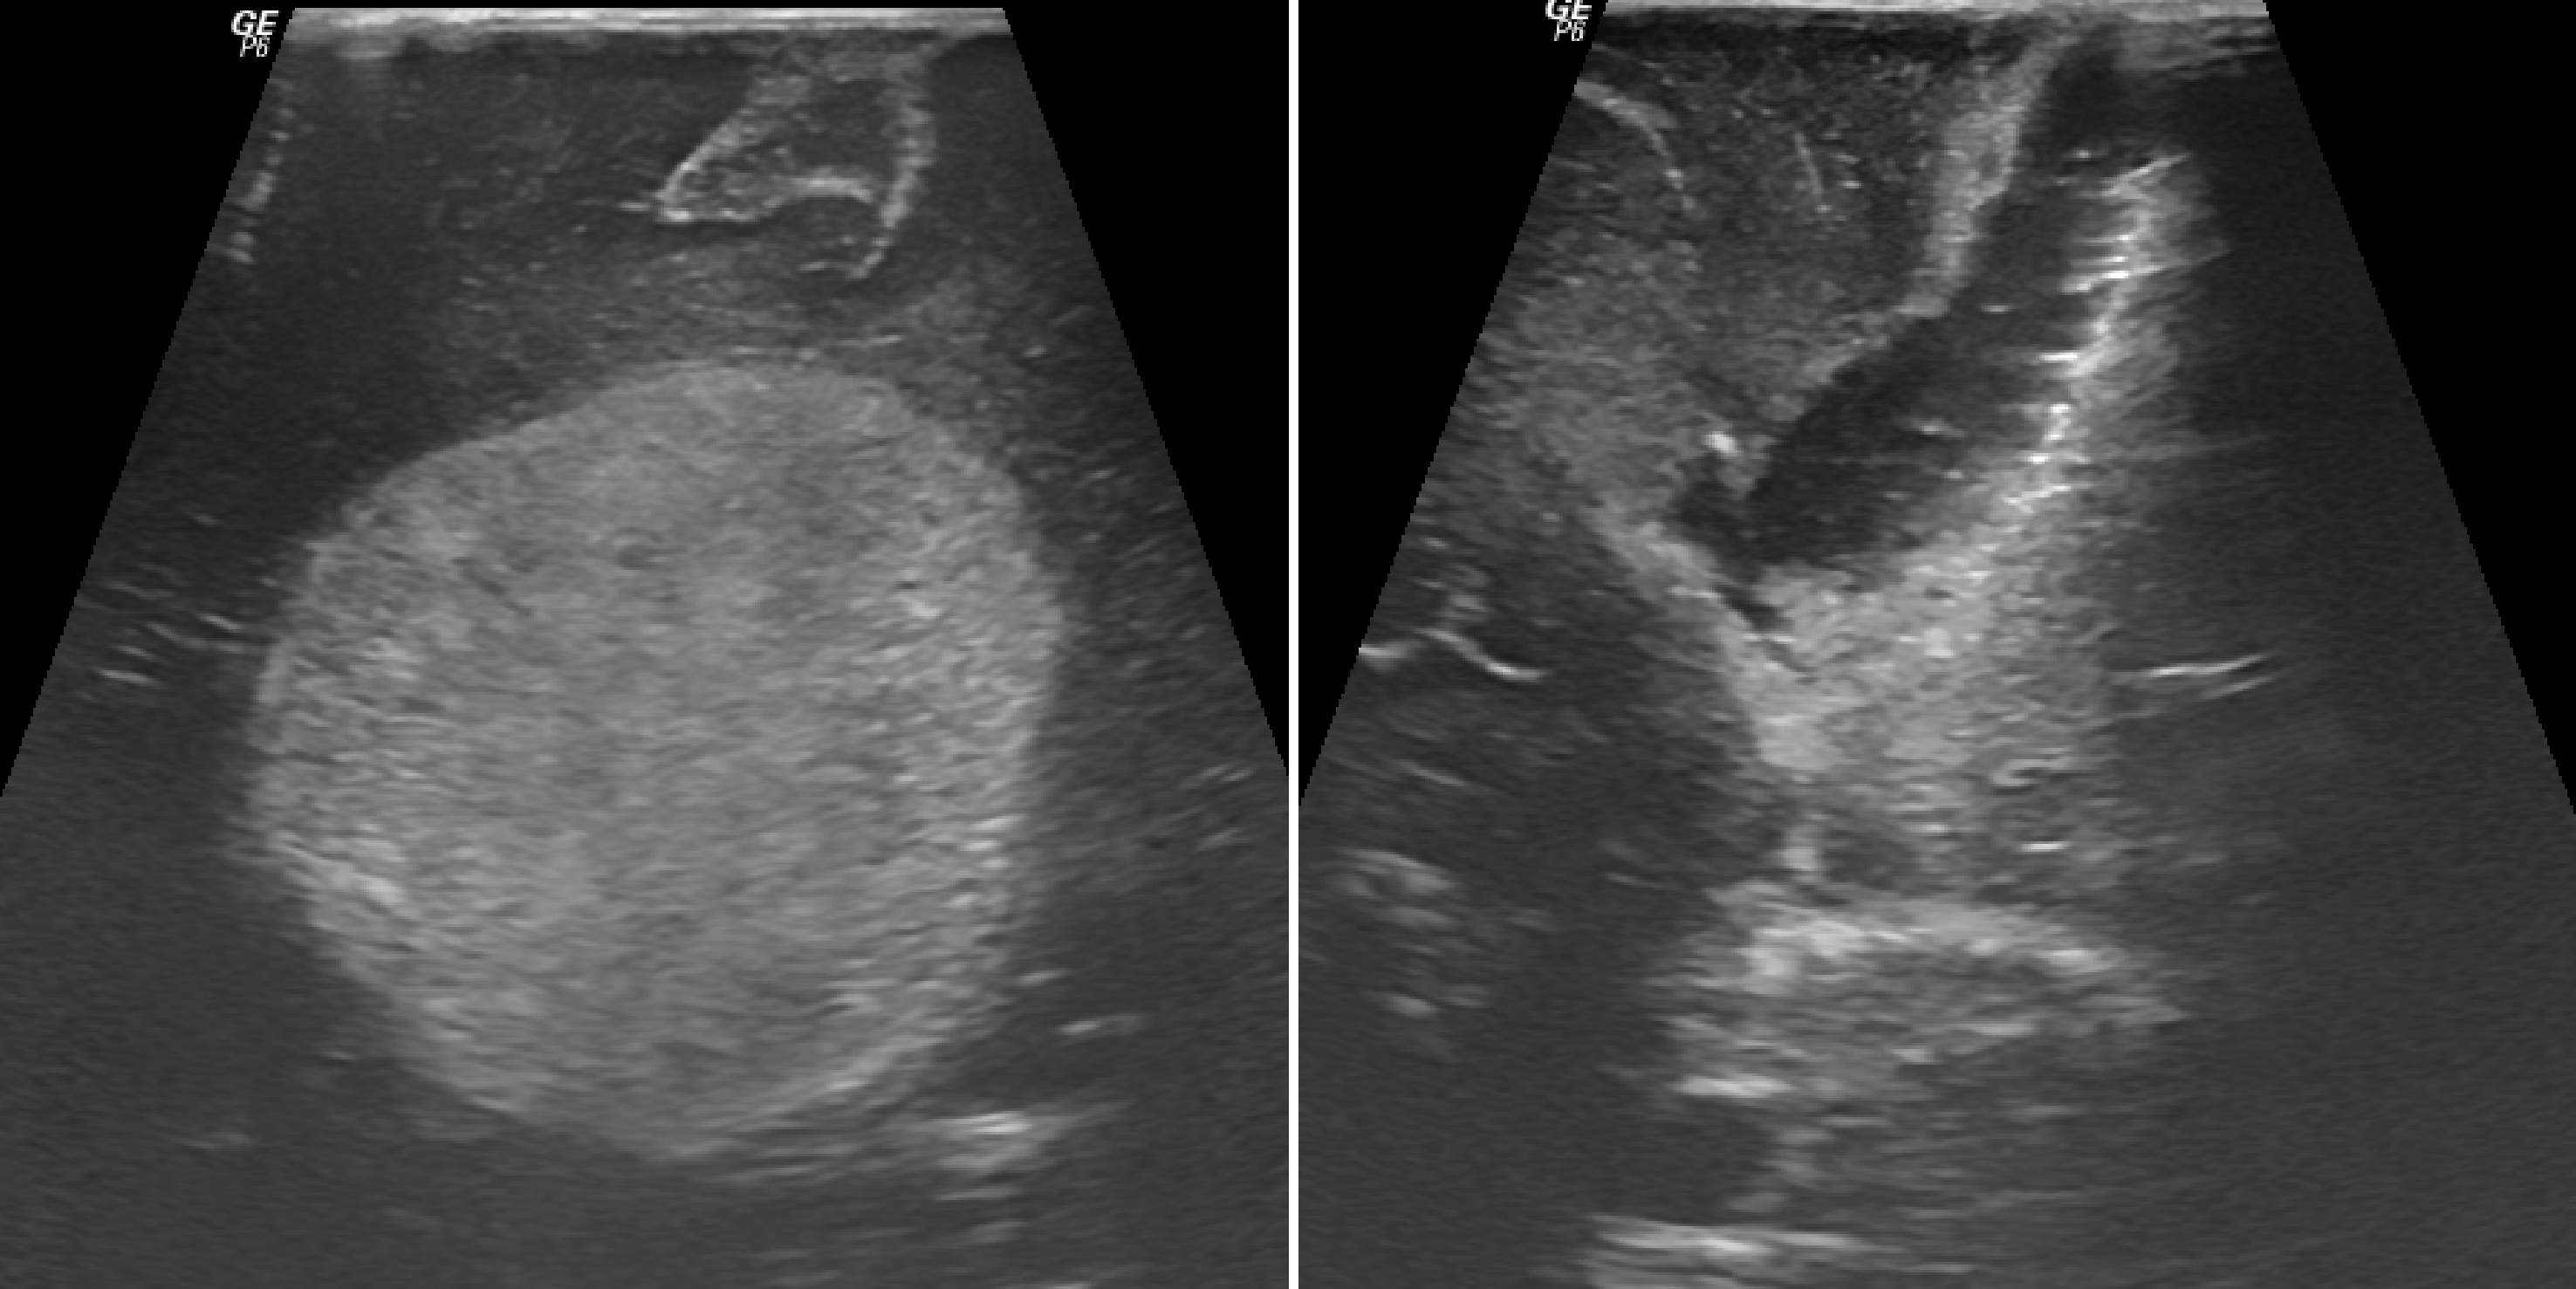

pre-operative

post-operative

Neuroultrasonography © ENI